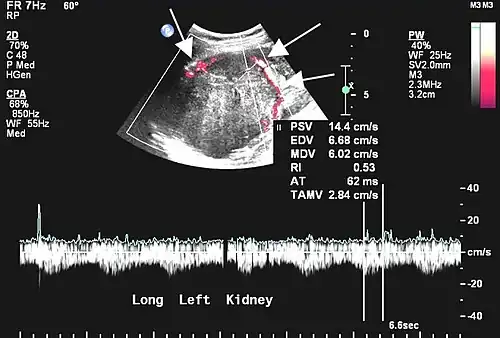

- Tumeur fibreuse solitaire du rein

Aspect tomodensitométrique. La tumeur est repérée par les flèches[46].

Aspect échographique. La vascularisation est visible en rouge, repérée par les flèches[46].